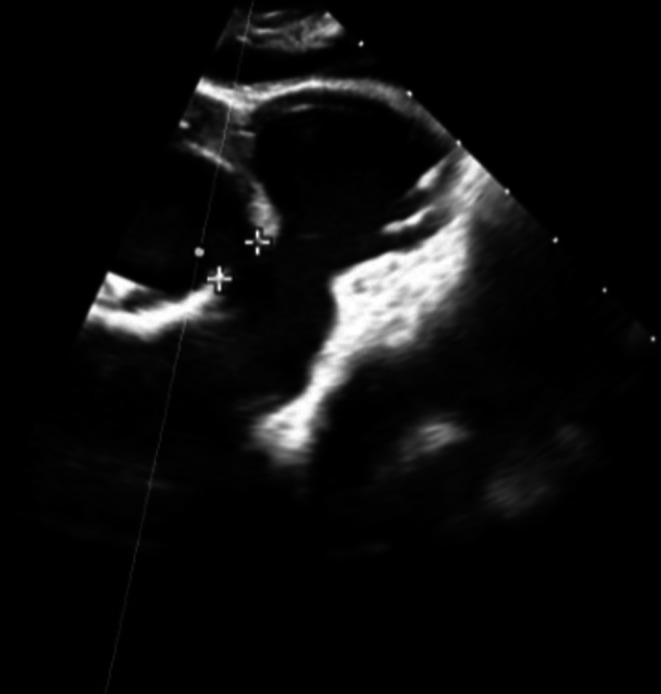

Spontaneous Resolution of Hemolysis After Ventricular Septal Defect Closure With an Amplatzer Device.

A wait and see approach can be maintained in cases with mechanical hemolysis after percutaneous VSD closure, even when the cause is not homogeneous.

对于经皮室间隔缺损封堵术后发生机械性溶血的病例,即使病因并不相同,也可采取观察等待的方法。